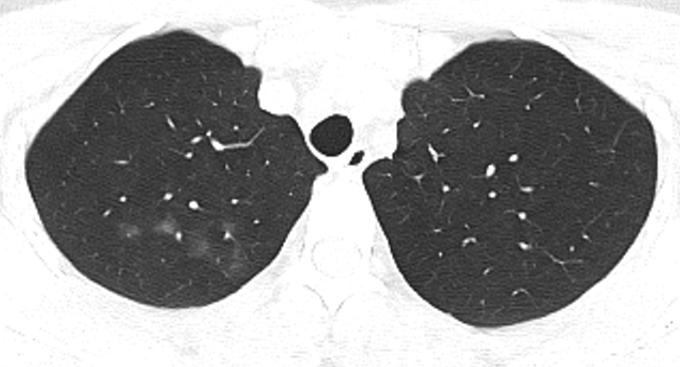

胸部CT示:双肺多发磨玻璃结节,左下叶背段散在实性结节,散在小空洞,部分支气管的管壁增厚,如下(图1~17)。